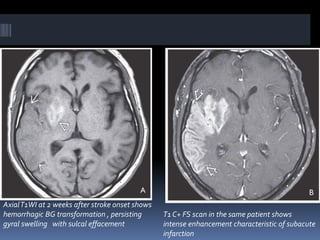

AxialT1WI at 2 weeks after stroke onset shows

hemorrhagic BG transformation , persisting

gyral swelling with sulcal effacement

T1 C+ FS scan in the same patient shows

intense enhancement characteristic of subacute

infarction